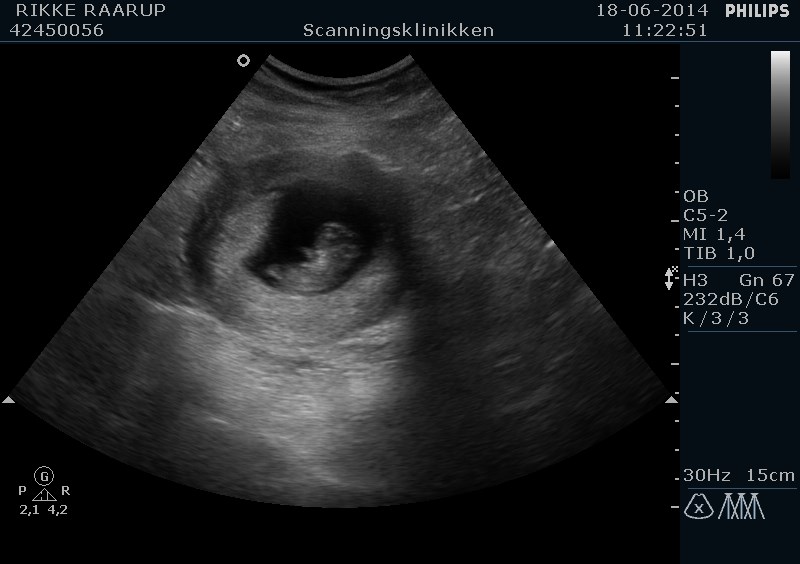

HELDIGVIS så vi den fineste lille babyspire. Målene passede til min udregning - 10+3. Vi så et fint hjerteblink og fin gennemstrømning. Grundet vores historie satte hun hjertelyd på Jep - crybaby

Vedhæftede fotos (klik for at se i fuld størrelse)